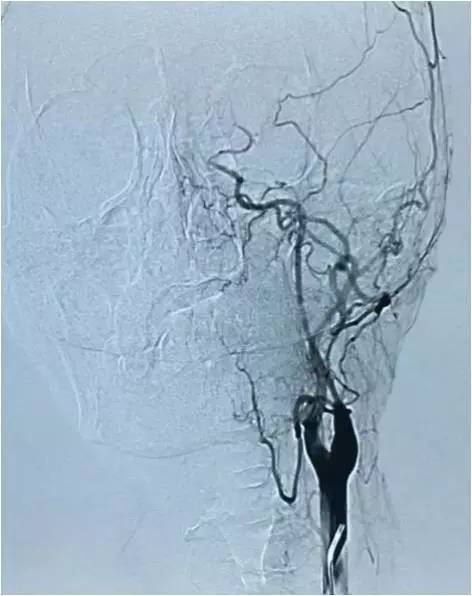

以下图像为DSA,显示基底动脉顶端动脉瘤,左侧小脑上动脉瘤,左侧PCA P1段微小动脉瘤,双侧颈内动脉眼动脉以远闭塞,前循环靠后循环通过后交通动脉代偿。

▼左颈总动脉造影正位